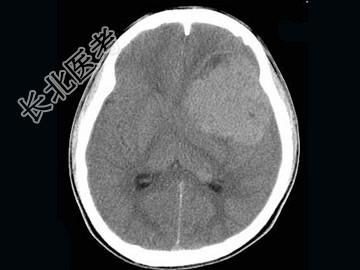

- 单项选择题男,15岁, 进行性头痛1年余,CT检查, 最可能的诊断为 ( )

A、脑膜瘤

B、脑血管畸形

C、转移瘤

D、淋巴瘤

E、胶质母细胞瘤